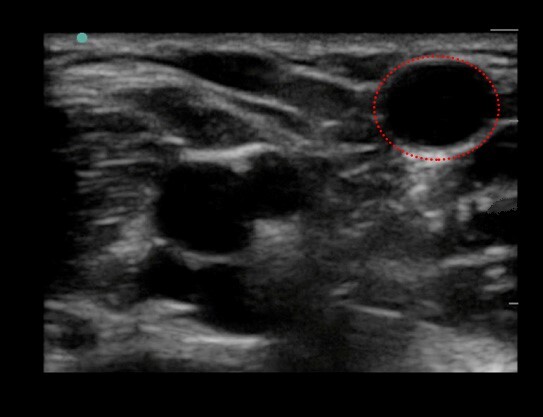

贵要静脉 1 图